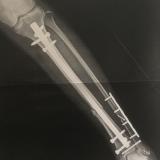

13交通事故で足の切断の危機から毎日1万歩!歩けるまでの挑戦足の切断の危機から半年の入院を経て歩けるようになるまでの軌跡を綴ります。-